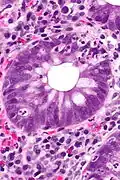

Crypt abscess. H&E stain.

Crypt abscess. H&E stain.